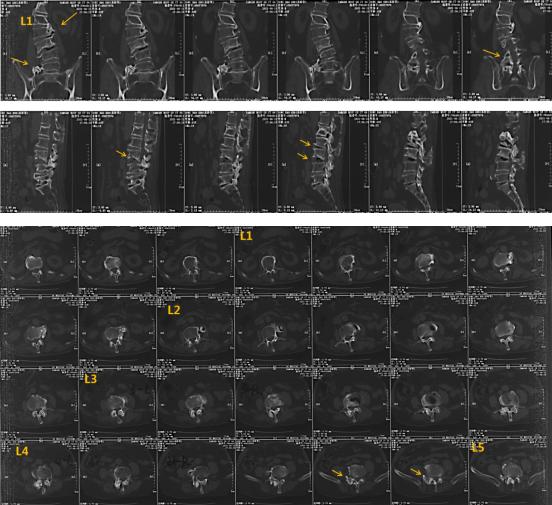

廖博主任对刘爷爷进行了详细的查体,发现他腰部脊柱右侧凸畸形,腰背部局部压痛、叩击痛,左下肢直腿抬高及加强试验阳性。在刘爷爷的影像学检查中,也可以明显观察到成人退变性脊柱侧凸畸形、腰椎管狭窄症、骨质疏松性压缩性骨折。

而从患者的核磁共振上可以观察到,腰3出现压缩性骨折,并且腰椎管出现狭窄。

CT